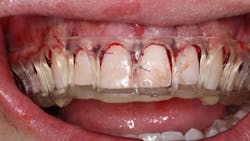

After seeing the great return on investment his brother received from Dr. Glassman’s New York City dental office, one patient seized the opportunity for a consultation of his own. As a healthy 22-year-old college student, the patient sought out dentistry to enhance his facial esthetics and offer his smile a well-deserved promotion (figure 1).

During the initial appointment, the patient stated that his objective was to lessen the amount of gums he displayed while smiling. Records were obtained, including facial photos, intraoral scan, and CBCT. Through quantitative analysis, the height-to-width ratio of his anterior central teeth was nearly 1:1, with the ideal ratio of width to height being 0.80. Also noted was the wear on the teeth. This caused the teeth to be 8 mm in length when they should be between 10 mm and 11 mm.

A series of diagnoses were made, which included excess vertical maxilla growth, altered active eruption, and hypermobility of the upper lip. The treatment plan included two parts: a “smile lift” by repositioning the maxillary alveolar crest apically and minimally invasive porcelain veneers on teeth nos. 4–13. This would add an additional 3 mm to the overall appearance of the central incisors as well as lengthening the additional teeth included in the treatment plan.